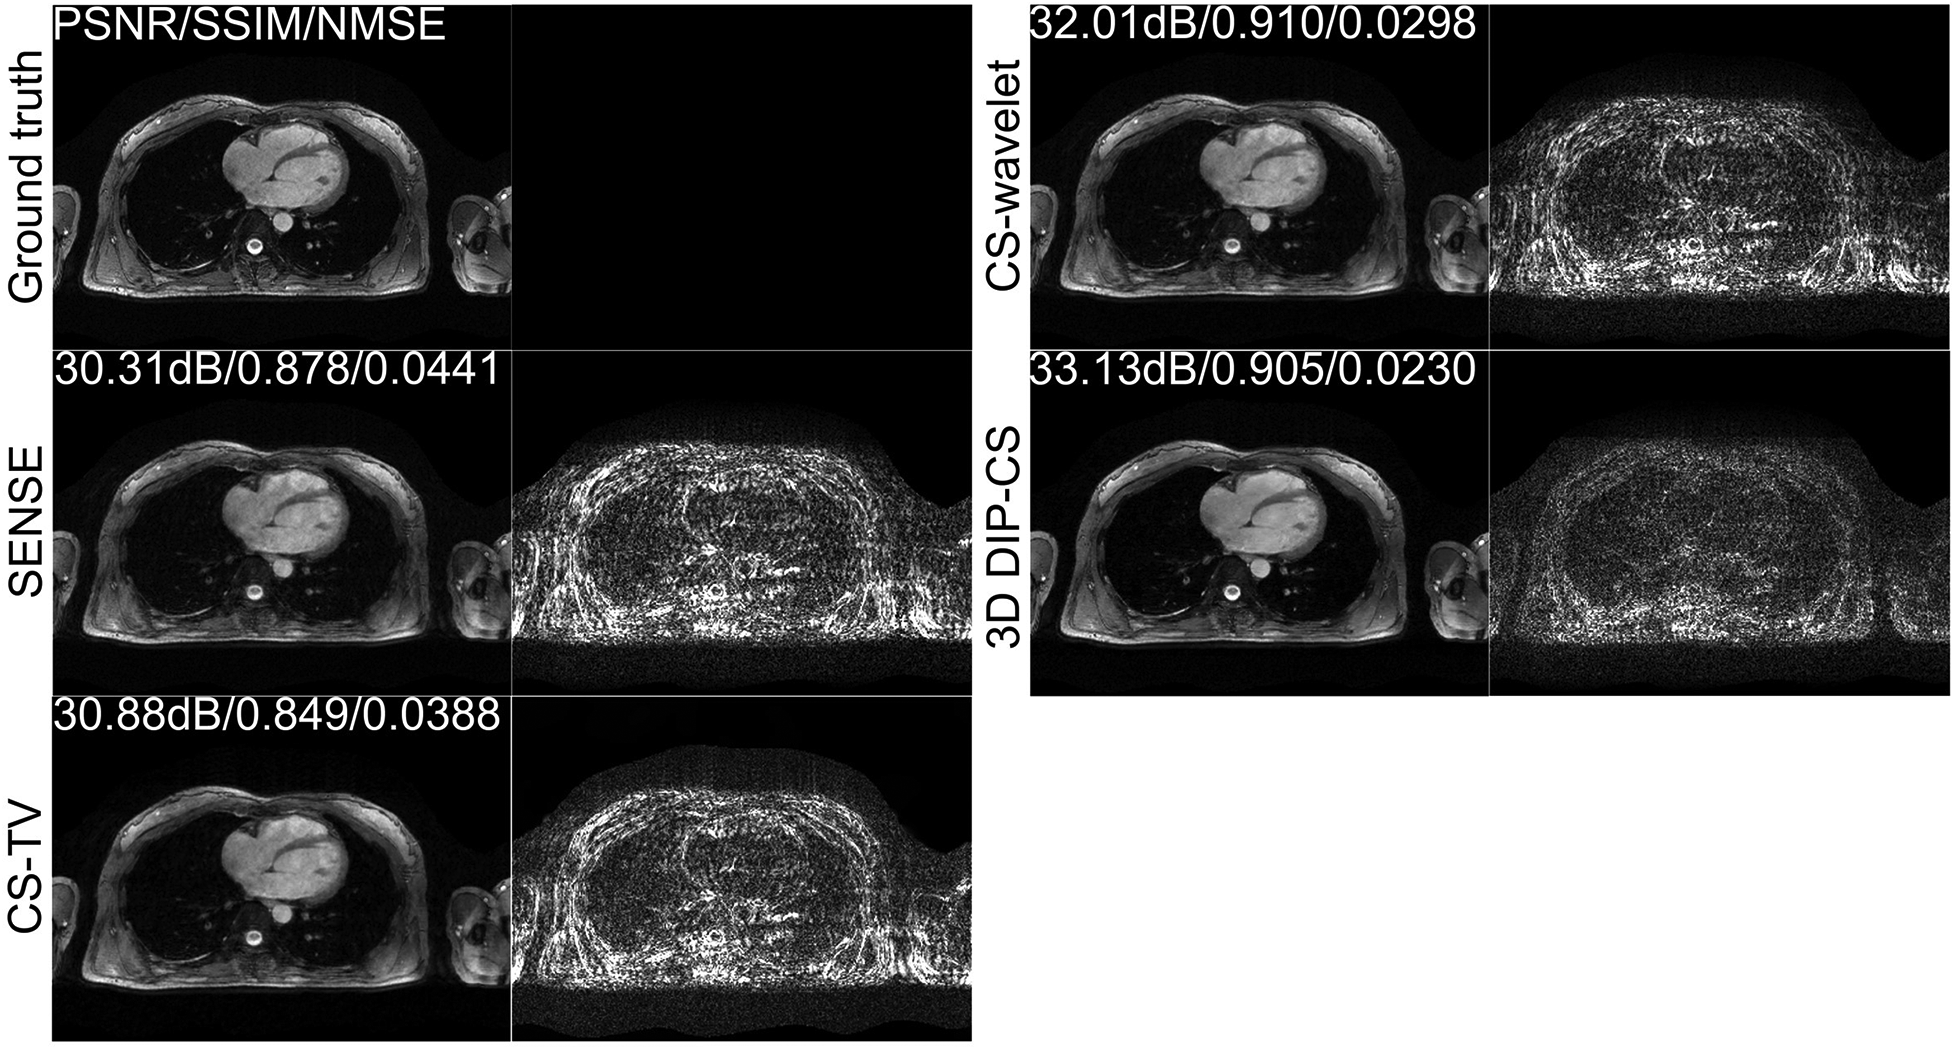

Figure 4 shows the comparison of iterative SENSE, CS-TV, CS-wavelet, and the proposed method on R = 8. Compared with the other two methods, DIP-CS produced results with fewer artifacts in the image and lower reconstruction errors. The quantitative values calculated from the entire volume were also in accordance with the visual perception. Figure 5 shows the statistical comparison of these quantitative metrics across 10 subjects. The 3D DIP-CS method achieved higher PSNR and lower NMSE (PSNR: 33.20 ± 1.63 dB; NMSE: 0.0236 ± 0.0087) compared with SENSE (PSNR: 30.75 ± 1.75 dB, P = 5 × 10−10; NMSE: 0.0424 ± 0.0186, P = 2 × 10−6), CS-TV (PSNR: 31.22 ± 1.87 dB, P = 3 × 10−6; NMSE: 0.0382 ± 0.0174, P = 6 × 10−5), and CS-wavelet (PSNR: 32.25 ± 1.76 dB, P = 2 × 10−5; NMSE: 0.0299 ± 0.0128, P = 4 × 10−4). Differences in SSIM between DIP-CS and CS-wavelet were not statistically significant (SSIM: 0.862 ± 0.038 vs. 0.864 ± 0.038, P = 0.57) in our experiments.

Figure 4

Reconstructions of CMRA in the transversal view from one representative subject, reconstructed with iterative SENSE, CS-TV, CS-wavelet, and the proposed 3D DIP-CS (R = 8). Corresponding error maps with respect to the fully-sampled ground truth are also shown. 3D DIP-CS led to improved reconstruction accuracy compared with these alternative methods.